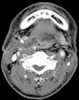

Tracheotomy (, UK also ), or tracheostomy, is a surgical procedure which consists of making an incision (cut) on the anterior aspect (front) of the neck and opening a direct airway through an incision in the trachea (windpipe). The resulting stoma (hole) can serve independently as an airway or as a site for a tracheal tube or tracheostomy tube to be inserted; this tube allows a person to breathe without the use of the nose or mouth. [Source: Wikipedia ]